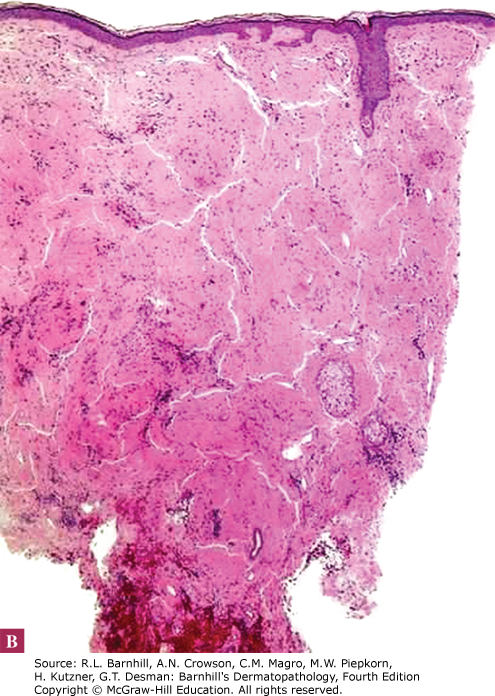

A 46-year-old male presents with a 6-month history of rash on his lower legs pictured below. He is otherwise well without any known medical conditions. Given the unclear etiology, you perform a biopsy showing the histology below. Which of the following would explain the findings seen on histology?

Differentiating between the different types of amyloid is important clinically and for test-taking purposes. Amyloidosis can be divided into systemic primary, systemic secondary, and localized. Genetic and hemodialysis-associated forms also exist. There are three main forms of localized cutaneous amyloidosis: macular, lichen, and nodular amyloidosis. Amyloid has green birefringence with polarized light when stained with Congo red as shown below.

Nodular amyloidosis presents clinically with brown-pink papules or nodules typically on the lower extremities/acral surfaces and the face. Histologically, amyloid deposits are found in the dermis, can extend into the subcutis, and are frequently found within vessel walls. Nodular amyloidosis is differentiated from the other two forms of localized cutaneous amyloidosis by the presence of AL protein derived from immunoglobulin light chains. Nodular amyloidosis has an approximately 7% risk of progression to systemic amyloidosis; therefore, these patients should be monitored closely. Additionally, nodular amyloidosis can be associated with autoimmune conditions, particularly Sjogren's syndrome, and patients should be screened accordingly.